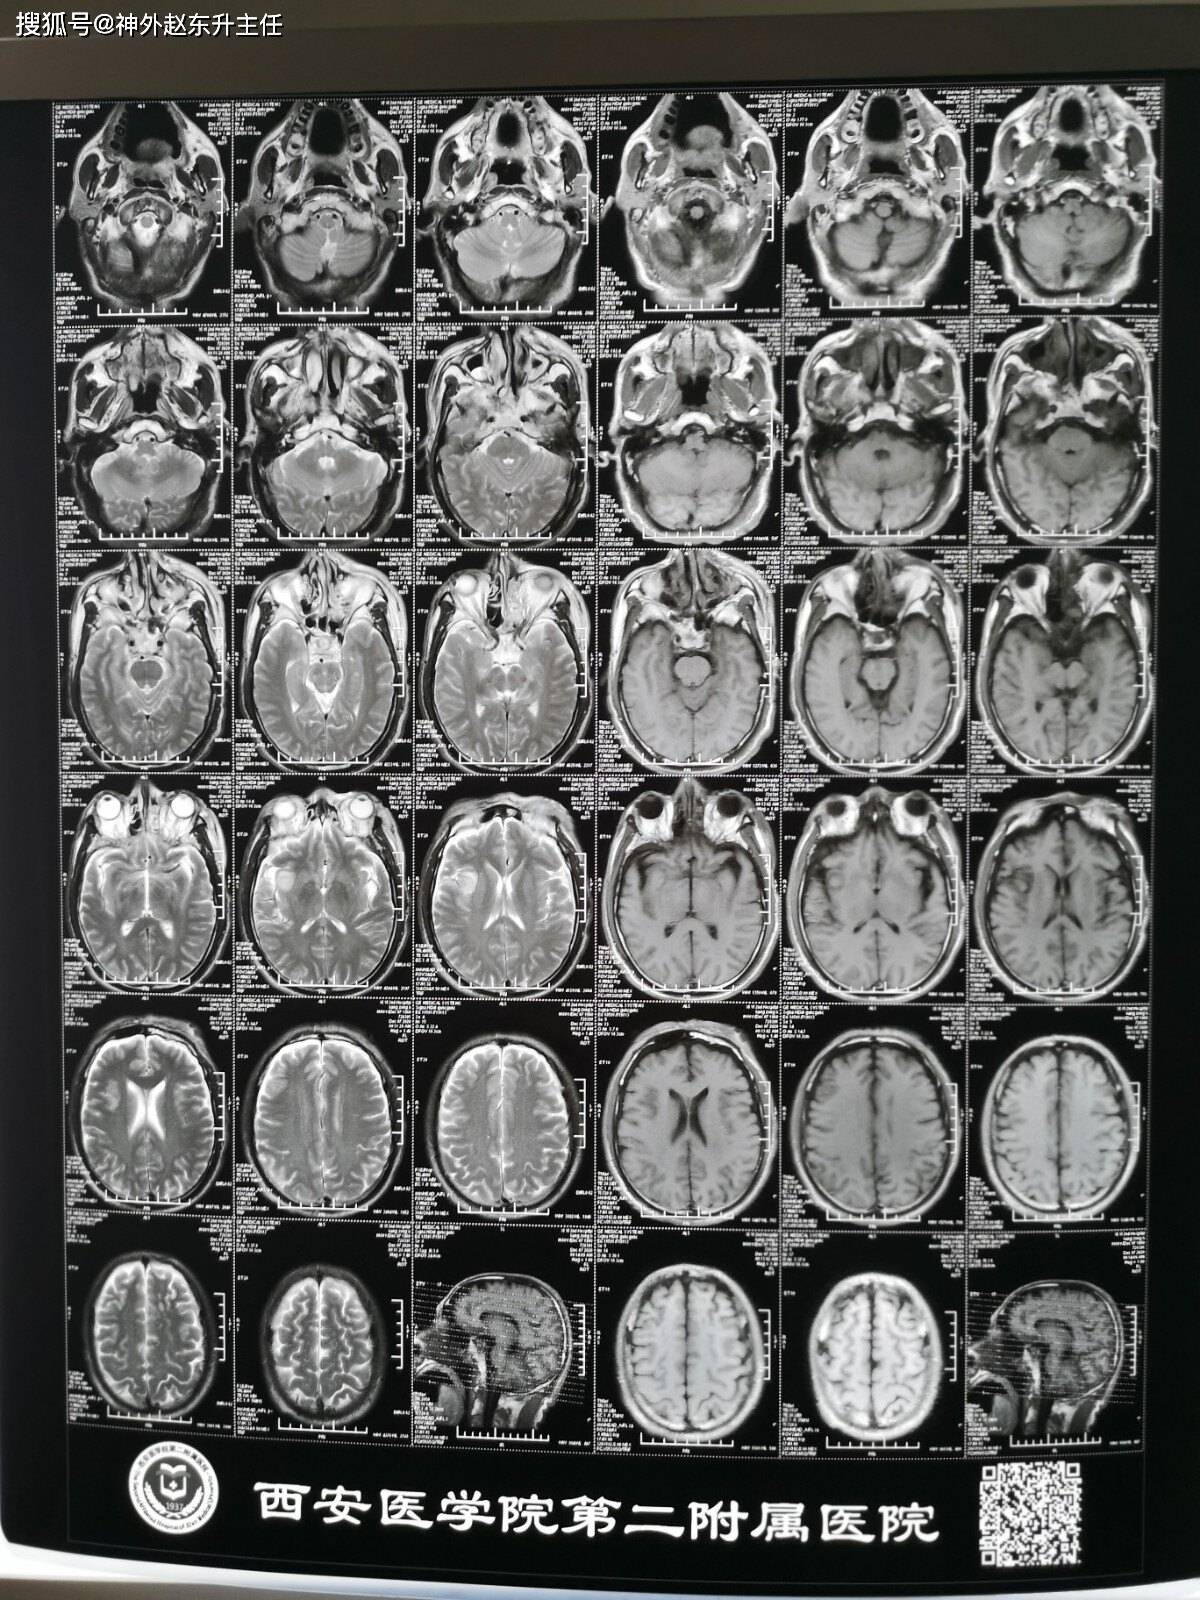

头颅核磁共振片子

头颅核磁共振片子,

看片子好像伤的不太重啊,右颞叶一点小挫伤,怎么患者昏迷程度那么深呢

收藏头颅核磁共振几个成像的意义

男,40岁,以前身体非常健康,近几天突然感觉头痛,做头颅核磁共振